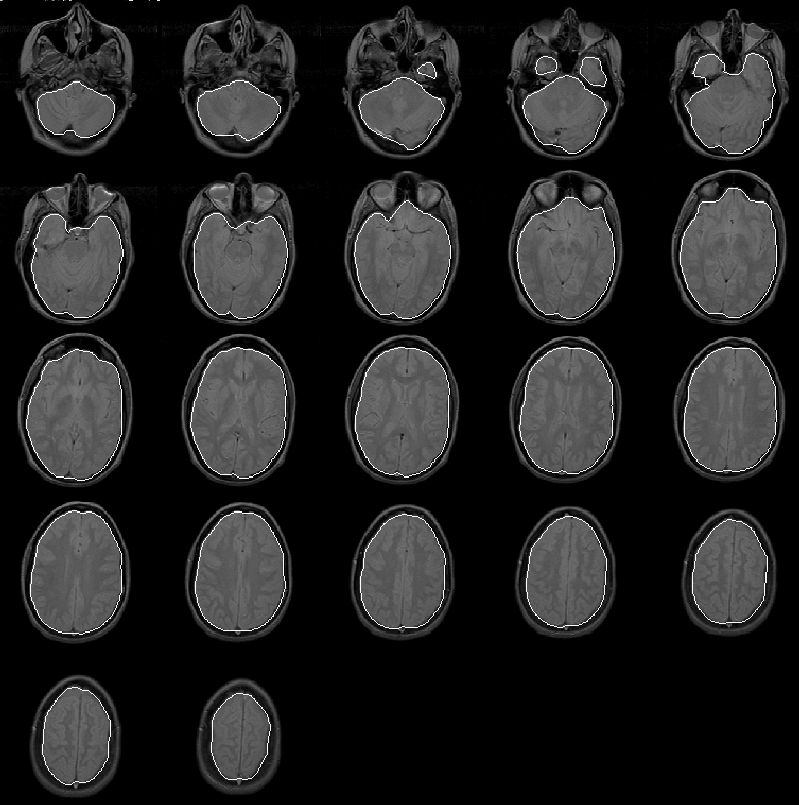

As with the final brain masks of the previous 4 data sets, the final brain mask produced for Data Set 5, shown in Figure 8.25 contains few remarkable errors. The mask misclassifies some small regions of extremely low intensity brain tissue, but is otherwise accurate. The mask will be quantitatively evaluated when expert information becomes available.

Figure 8.25: The final brain mask for MRI Data Set 5 overlaid on the PD-weighted scan.